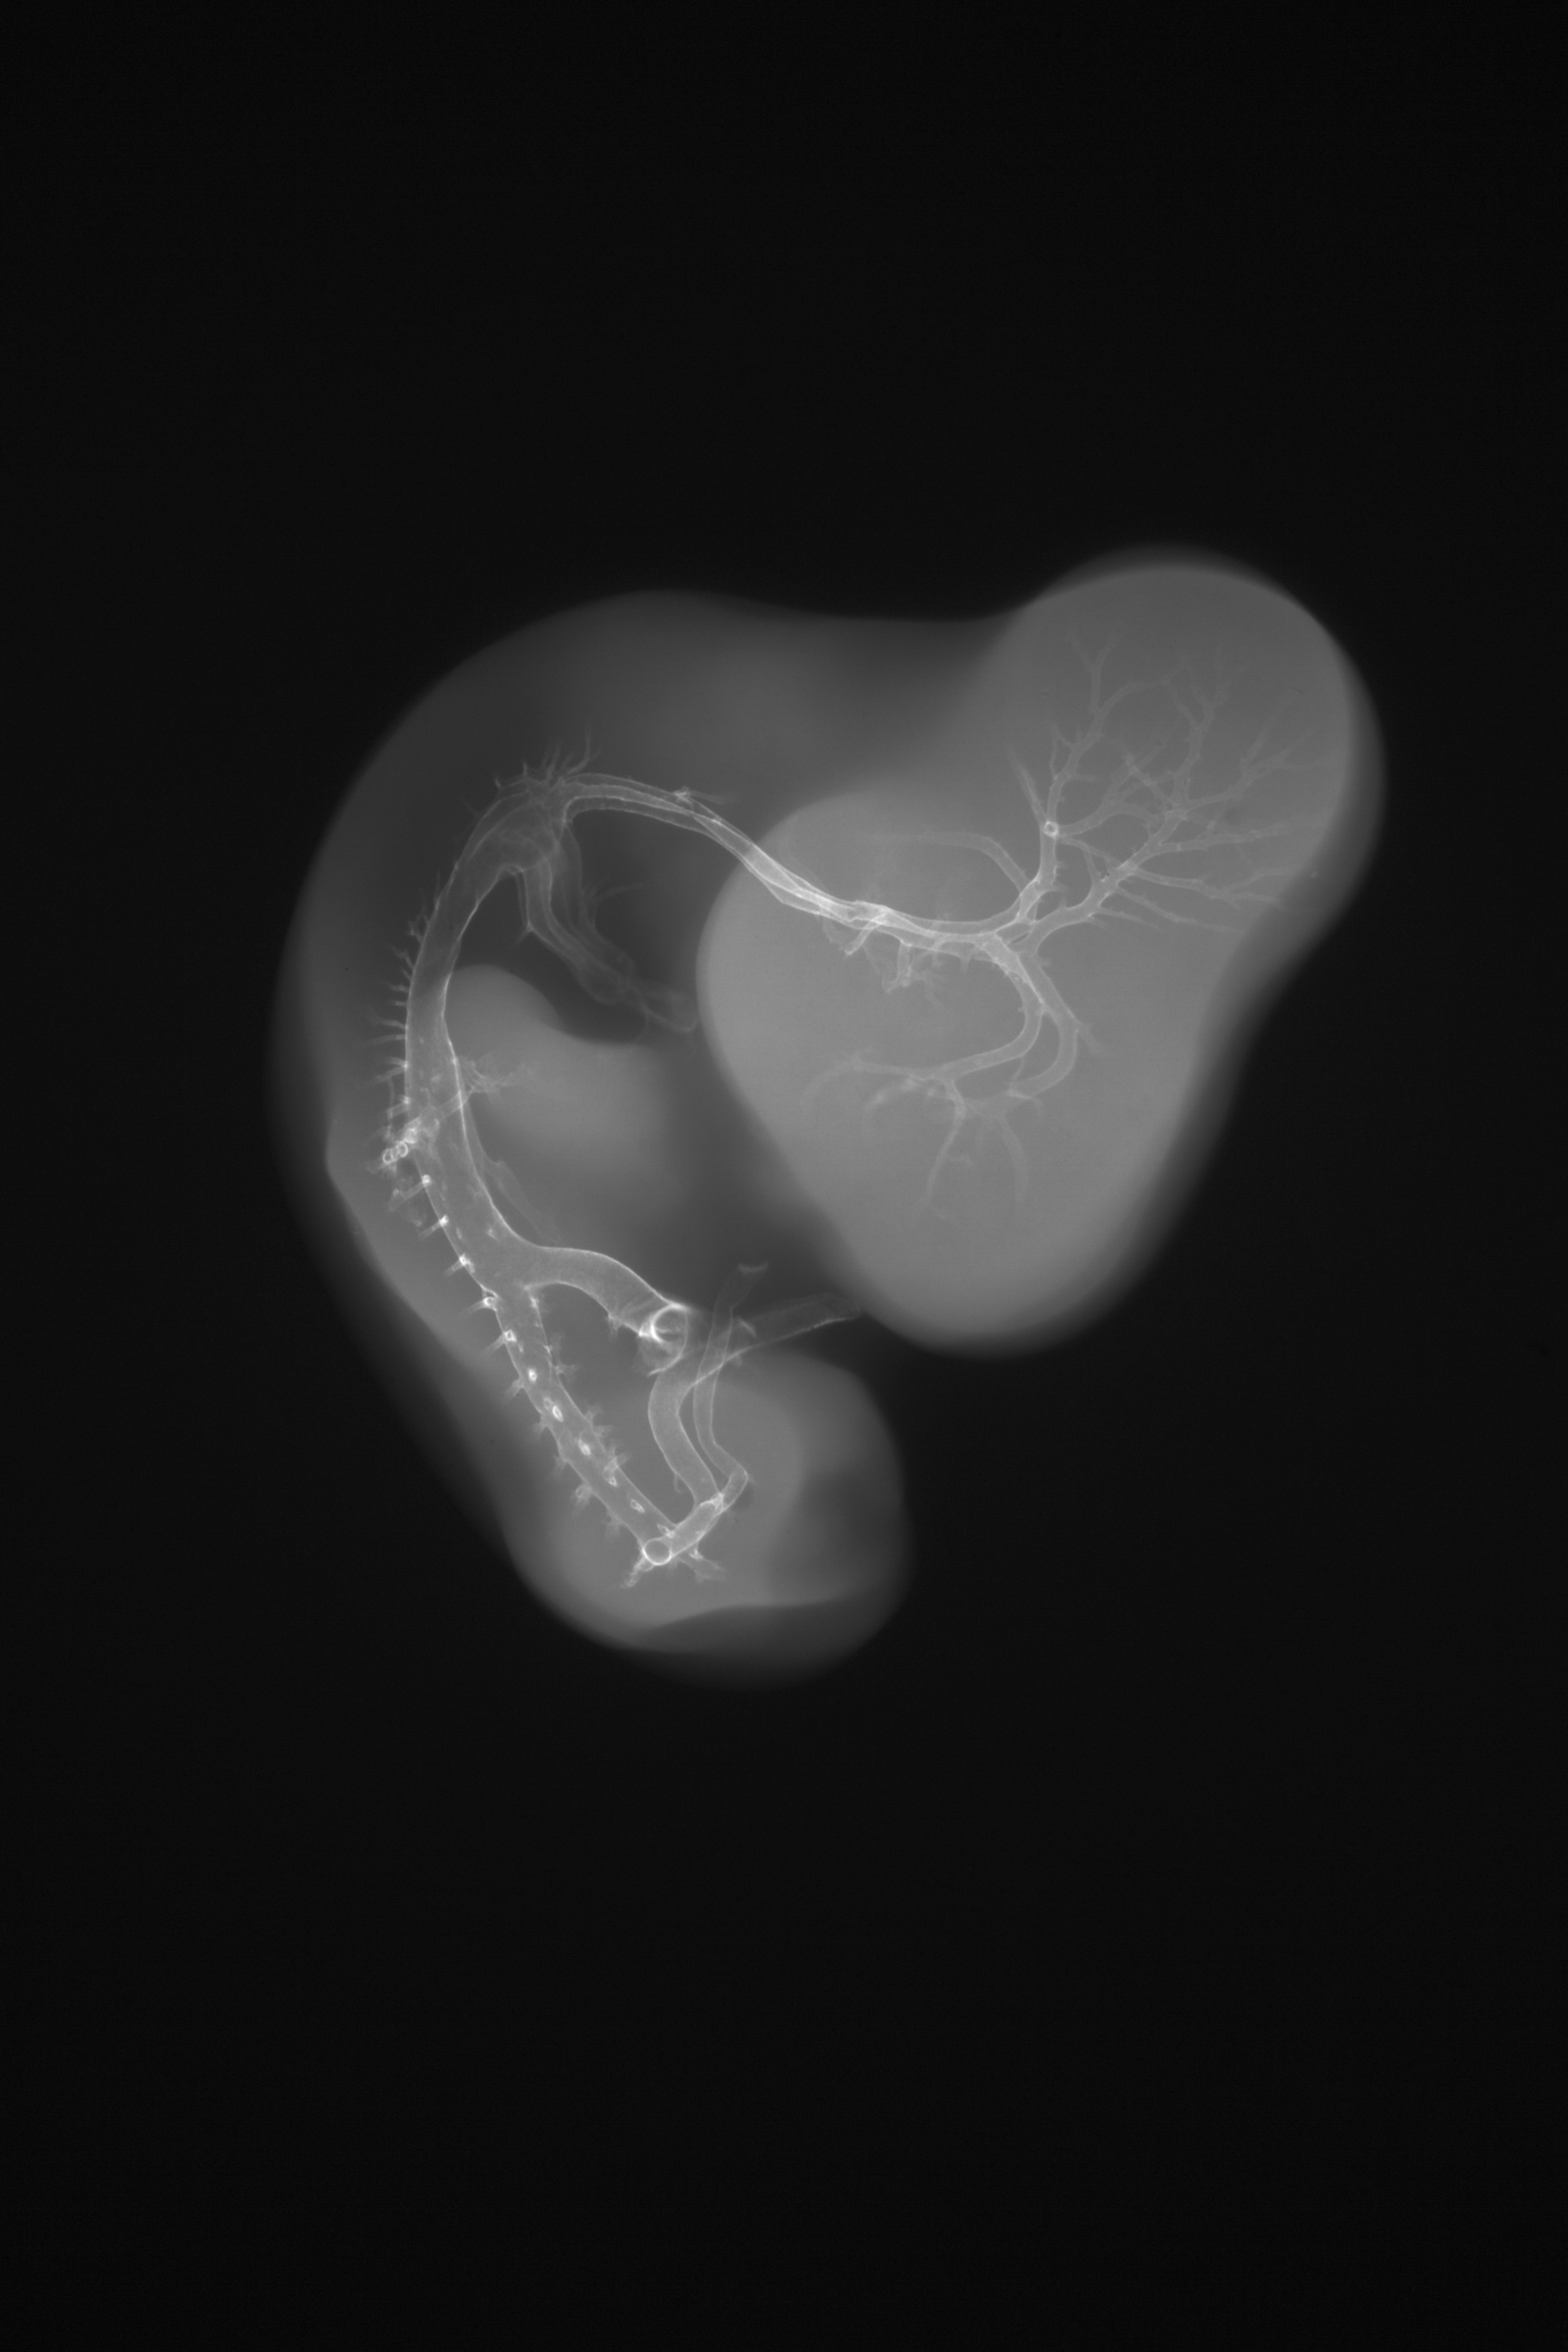

Chick Embryo Microangiography

Hamburger-Hamilton (HH) Stage 27 (approx. 5 - 5.5 days)

X-Ray Micrographs